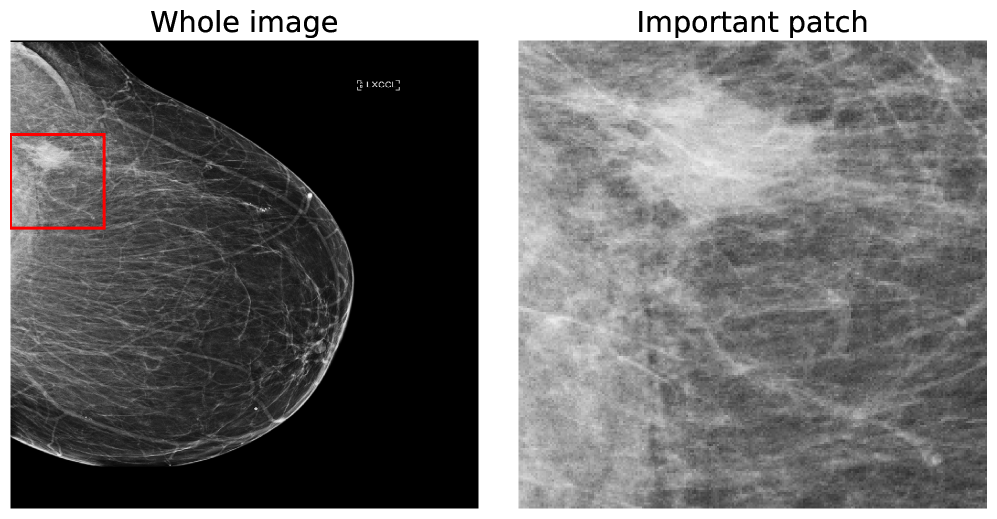

A further benefit of our approach is that the concept vectors can be used to gain an interpretable component about what the model is learning to look for. We can do this by showing example patches that correspond to the ’th concept vector activating and having the maximal response, i.e., making the classification determination. We provide an example for the first five concept classes on the BTMD dataset in Figure 4 and the RSNA-SMBC dataset in Figure 5. In both cases, the row corresponds to a concept, and 25 columns show 25 winning exemplars.

The BTMD dataset has considerably more visual variation in the images, making them more challenging to inspect as non-medical experts, but visual themes are generally discernible across each row in Figure 4. We note that there is no mechanism to force one concept vector to suppress other concept vectors for similar activations, and so we see some cross-pollination between the concept vectors. The RSNA dataset has less visual asperity, and visual patterns are more clearly observed in the rows of Figure 5.

In Figures 7 and 8, we display more representative patches selects that correspond highly to a given concept vector (one concept per row), highlighting our our method automatically learns sub-regions of the larger image space.